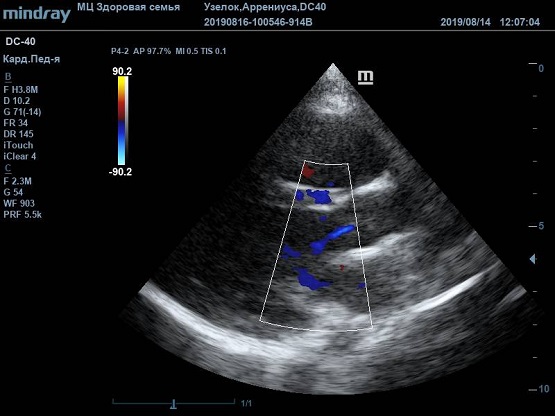

Найти их очень просто, достаточно сечений LAXLV (длинная ось) и SAXBASE (короткая ось). Специфические крупные шаровидные структуры – узелки Аррениуса - на кончиках полулуний клапана обнаружил ультразвуковой прибор Mindray DC-40. В цветовом допплере без труда определяется аортальная регургитация легкой степени. Оценить её можно в CFM по соотношению JW/LVOT.

Приборы среднего класса прекрасно справляются с этой задачей. Чтобы использовать возможности прибора на максимум необходимо уменьшить поле обзора (Front of view - FOV), тогда увеличится частота кадров и качество картинки при поиске мелких структур. Также частота кадров увеличивается при снижении уровня persistence, что актуально для детского возраста и высокой частоты сокращения сердца.